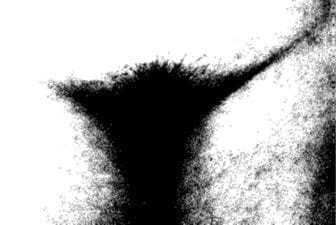

La silla turca mostró un aumento de tamaño en proyección lateral, sin evidencia de procesos erosivos, mientras que la politomografía mostró aumento de volumen con adelgazamiento del piso en algunos cortes (Fig.1).

Fig. 1. Politomografía de silla turca que muestra aumento de volumen con adelgazamiento del piso en algunos cortes, consistente con el diagnóstico de prolactinoma.